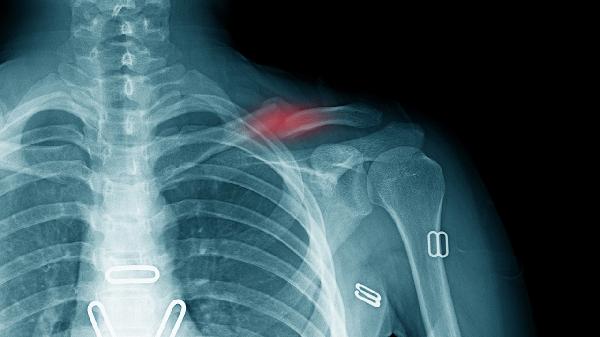

钩状骨骨折后,若为无移位的稳定性骨折且采用石膏固定保守治疗,通常6-8周可达到临床愈合标准。此阶段需定期复查X线确认骨痂形成情况,固定期间应避免腕关节负重活动,但需保持手指屈伸锻炼以防止关节僵硬。部分患者可能伴随局部肿胀或轻度疼痛,可通过抬高患肢和冰敷缓解症状。

若骨折存在明显移位或合并周围韧带损伤需手术复位内固定,恢复期可能延长至8-12周。术后早期需进行被动关节活动度训练,4周后逐步增加主动康复训练强度。开放性骨折或合并神经血管损伤者,因组织修复复杂,康复周期可能超过12周。延迟愈合者需考虑脉冲电磁场或超声波等物理治疗促进骨愈合。